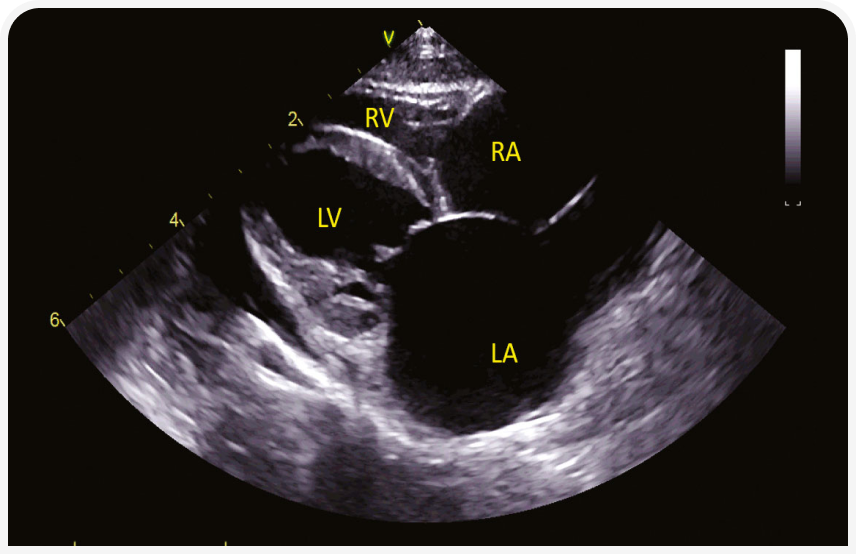

2. Рестриктивная кардиомиопатия (РКМП). РКМП без гипертрофии и расширения полостей или сопровождающаяся дилатацией левого или обоих предсердий (Рисунок 4) с диастолической дисфункцией, рестриктивным характером наполнения сердца, характеризуется более чем в два раза более высокой скоростью трансмитрального потока Е по сравнению со скоростью волны А. Обратите внимание, что эта форма диастолической дисфункции неспецифична для РКМП, но может возникать при любой кардиомиопатии. Подразделяется на миокардиальную форму (22), без особенностей эндокарда (Рисунок 4), и эндомиокардиальную форму (23, 24), при которой эндокард может быть неравномерно утолщенным и эхогенным, с рубцовыми мостиками, которые могут вызывать внутрижелудочковую обструкцию (Рисунок 5). Предрасположенность описана для кошек сиамской или ориентальной пород.

(b) RPS-проекция по короткой оси на уровне папиллярных мышц у той же сиамской кошки, что и на рисунке (5a). Эхогенный мостиковый рубец пересекает полость ЛЖ (стрелки).

5. Аритмогенная кардиомиопатия правого желудочка (АКПЖ) (25). Обычно преимущественно развиваются симптомы П-ЗСН и дилатация правых отделов сердца. Однако часто нарушается функция левого желудочка. Это может быть связано с желудочковыми или другими аритмиями. В отличие от собак или человека, у кошек при АКПЖ может возникнуть полная атриовентрикулярная блокада. Предрасположены кошки бирманской породы (Рисунок 8).

(b) Парастернальная четырехкамерная проекция справа по длинной оси у бирманской кошки с диагнозом АКПЖ с бивентрикулярной сердечной недостаточностью и АВ-блокадой 3-й степени. Все четыре камеры расширены, левый желудочек гипокинетичный.